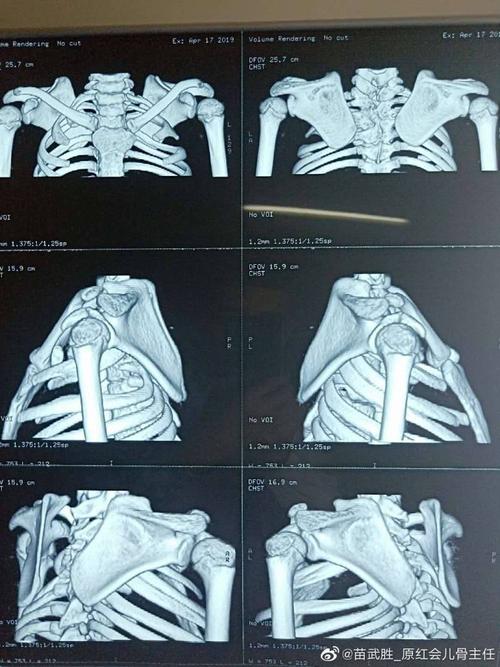

先天性高肩胛术后照片,高肩胛骨症孩子图片

近期做的先天性高肩胛术前术后照片

高肩胛骨症孩子图片

先天性高肩胛骨症图片